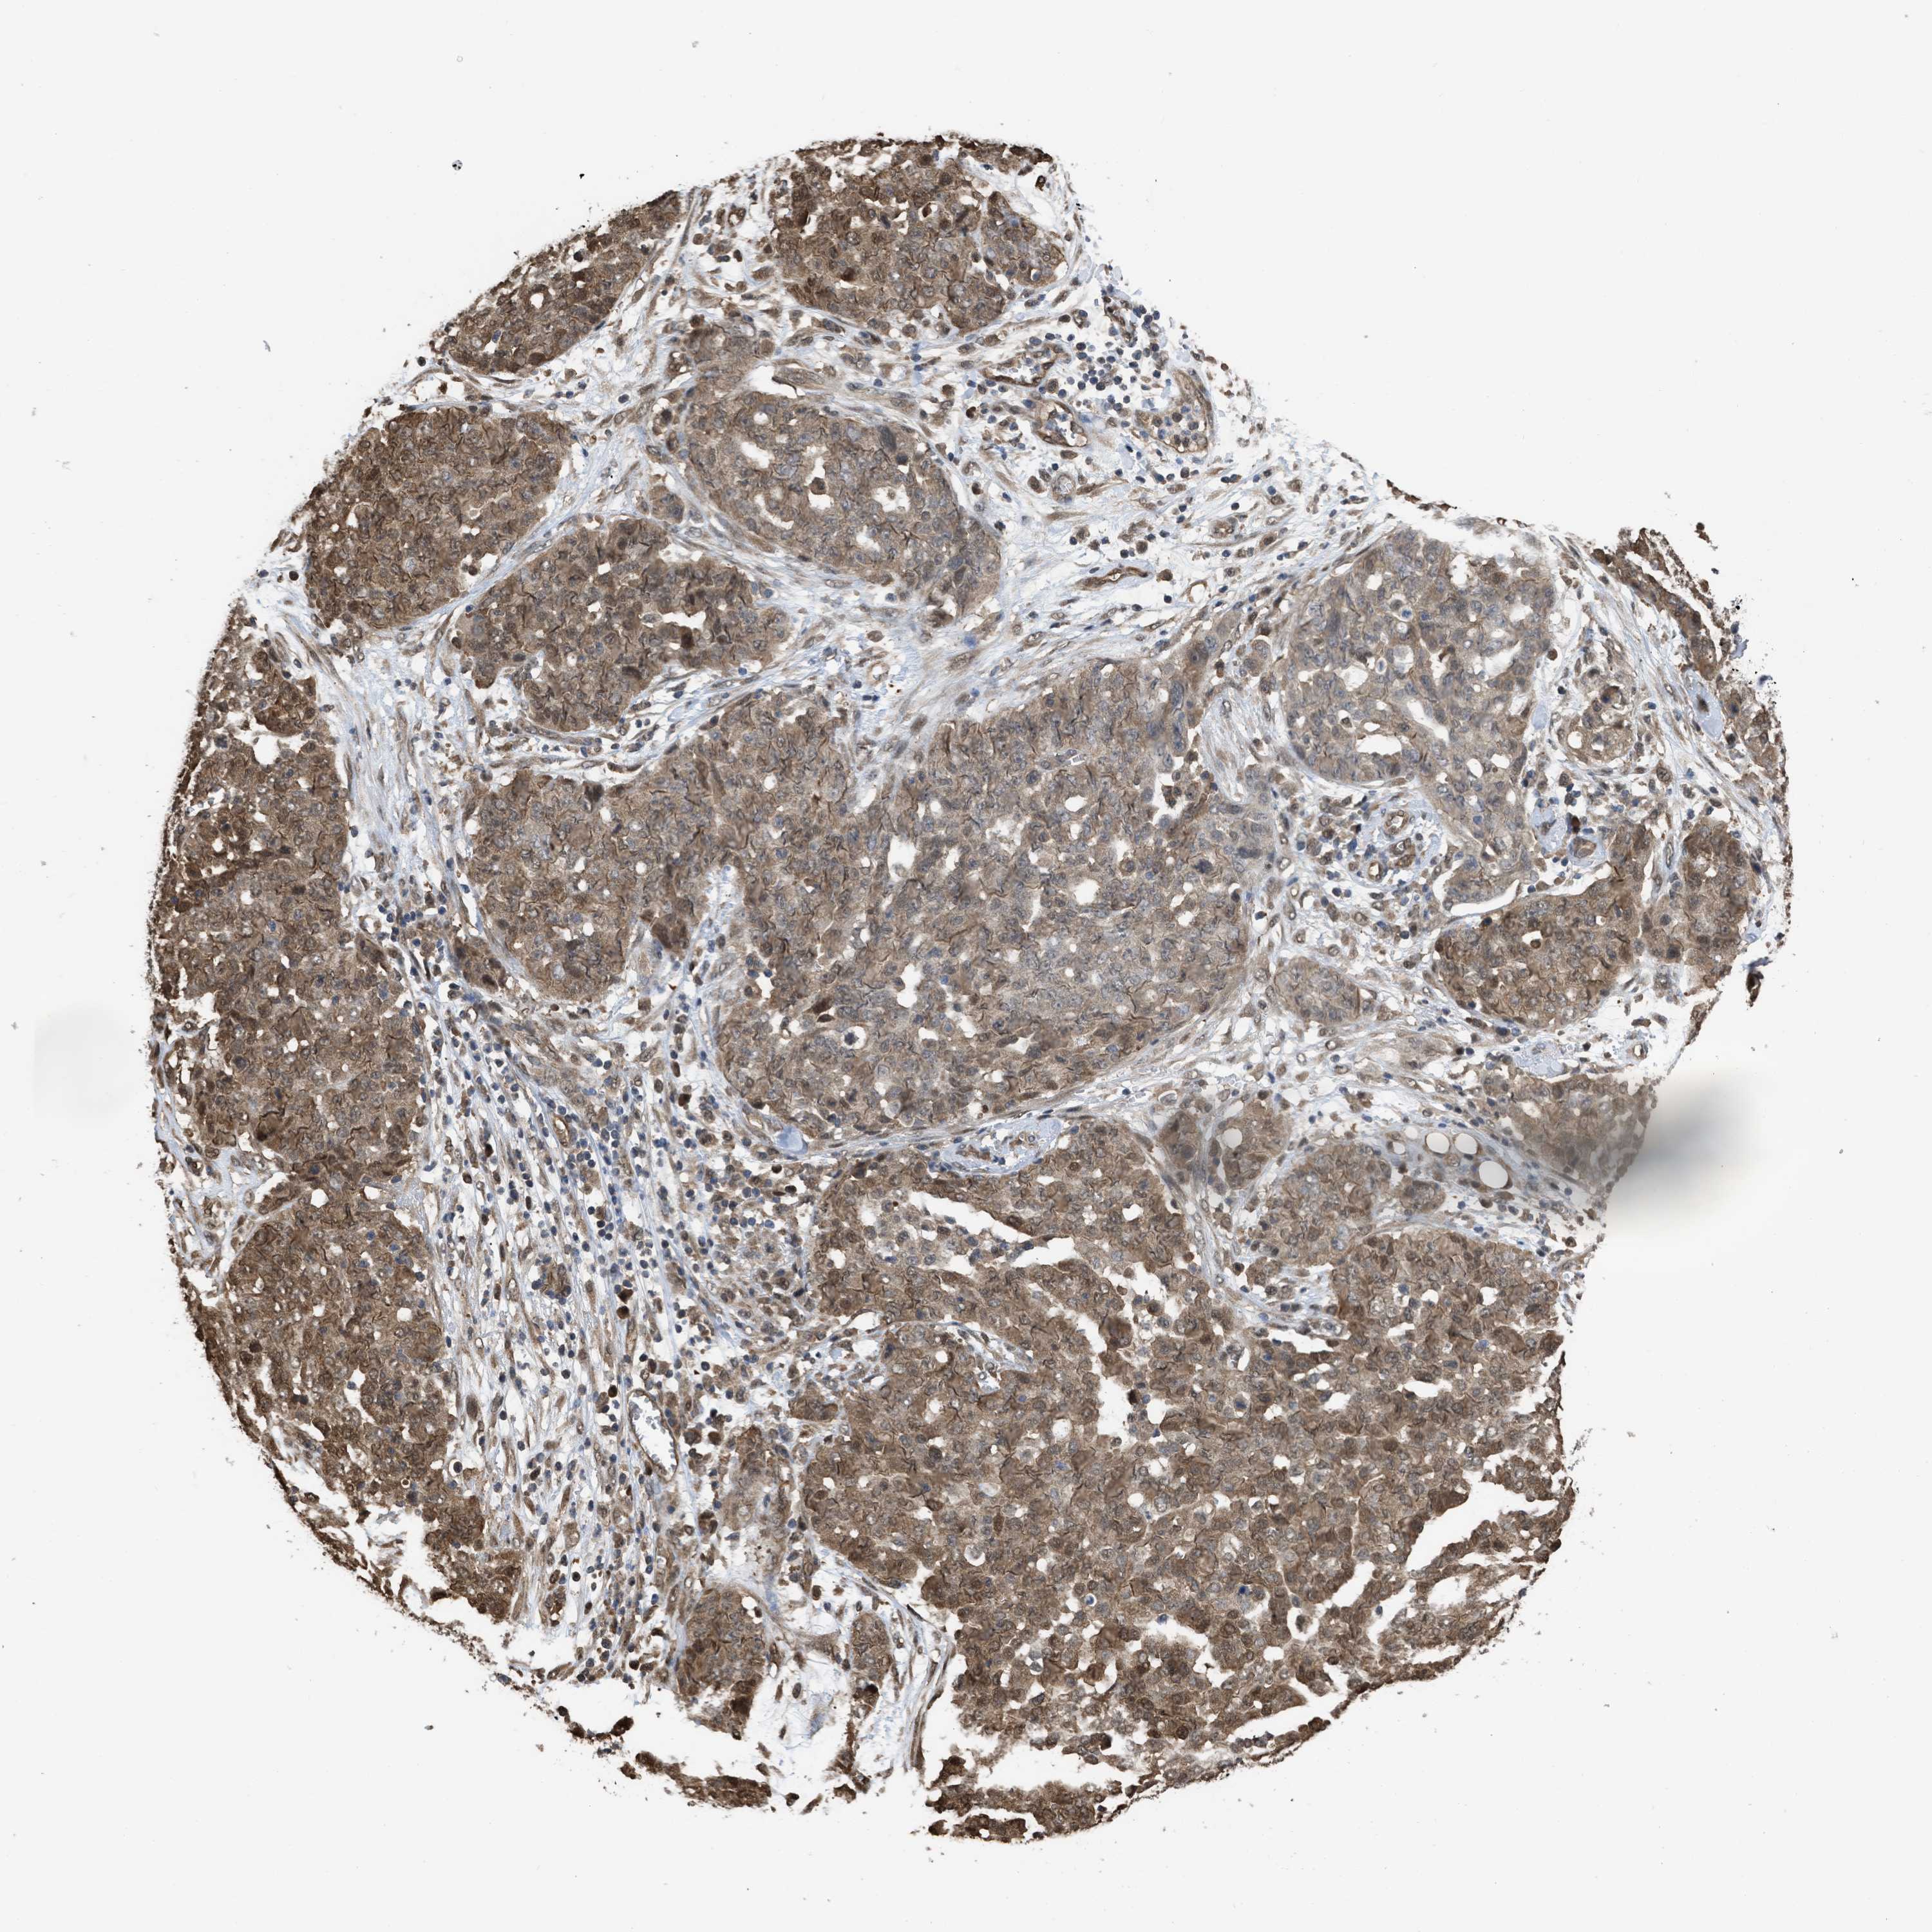

OVARIAN CANCER - Protein expressioni

A mouse-over function shows sample information and annotation data. Click on an image to view it in a full screen mode. Samples can be filtered based on level of antibody staining by selecting one or several of the following categories: high, medium, low and not detected. The assay and annotation is described here.

Note that samples used for immunohistochemistry by the Human Protein Atlas do not correspond to samples in the TCGA dataset.

Antibody stainingi

Antibody staining in the annotated cell types in the current human tissue is reported as not detected, low, medium, or high, based on conventional immunohistochemistry profiling in selected tissues. This score is based on the combination of the staining intensity and fraction of stained cells.

Each image is clickable and will lead to virtual microscopy that enables deeper exploration of all samples and also displays staining intensity scores, fraction scores and subcellular localization as well as patient and tissue information for each sample.

Antibody HPA026918

Antibody CAB013274

Antibody CAB018389

Staining

High

Medium

Low

Not detected

Carcinoma, endometroid